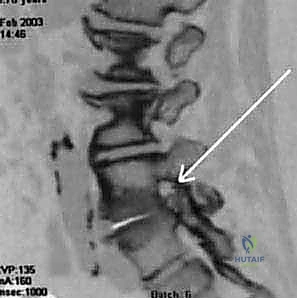

2. التصوير بالرنين المغناطيسي (MRI): هو المعيار الذهبي لتشخيص تضيق القناة الشوكية. يوفر صوراً ثلاثية الأبعاد وعالية الدقة للأنسجة الرخوة، بما في ذلك الأقراص، الأربطة، والأعصاب، مما يسمح للطبيب برؤية مكان ومقدار الضغط بدقة متناهية.

3. التصوير المقطعي المحوسب (CT Scan): يُستخدم لتقييم الهياكل العظمية بشكل أفضل، مثل النتوءات العظمية وسماكة العظام. غالباً ما يُستخدم للمرضى الذين لا يمكنهم الخضوع للرنين المغناطيسي.

4. الأشعة السينية (X-Rays): تساعد في استبعاد المشاكل العظمية الأخرى مثل الكسور، الأورام، أو الانزلاق الفقري، وتظهر التغيرات التنكسية العامة.

5. تخطيط كهربية العضل (EMG): في بعض الحالات، قد يُطلب هذا الفحص لتحديد العصب المتضرر بدقة وقياس مدى سرعة انتقال الإشارات العصبية.

تشخيص تضيق القناة الشوكية بالأشعة